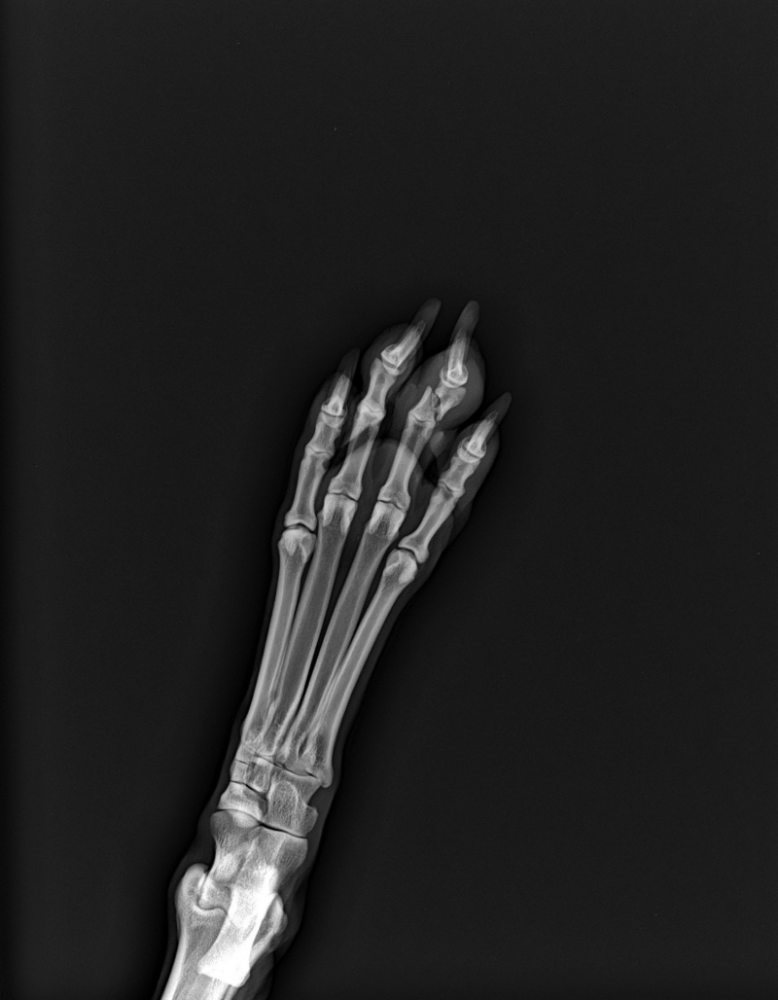

Mosfilmka & Remy Опубликовано 2 марта, 2023 Автор Опубликовано 2 марта, 2023 Во вторник мы побывали на обследовании у кардиолога, офтальмолога, сделали УЗИ, сдали кровь и показались хирургу. И как же хорошо, что сначала заглянули к хирургу! Новости очень хорошие!!! Нет у нас никакого разрыва, живые связки, а есть сломанный пальчик. Нет у нас никакого гипертиреоза, который показал результат анализа в клинике Владимира, гормоны в норме! Но меня разрывает злость и недоумение – ну как так?? Долбанная региональная ветеринария, нам поставили разрыв ПКС при сломанном пальчике!! Я ведь вспоминаю еще, что предлагала сделать рентген всей лапки, и он нормально пальчики по отдельности не посмотрел, пожмякал только все, реакции не было и он не стал проверять каждый. Ну ладно мы, перепроверяем у других врачей диагнозы, а как тогда он диагностирует других пациентов?? Другие бы через неделю приехали к нему на операцию, потому что хромота сохраняется. И он бы ее, получается, провел... Комолов Мэй похвалил, сердце хорошее, противопоказаний нет к операции. Удалять папилломы с век и новообразование на плече нужно в самое ближайшее время (на правом глазу маленькая папиллома прямо у слезной точки и при росте ее перекроет), а также сдать это на гистологию. Папилломы действительно стали чесать роговицу, доктор сказала - да, вижу следы свежие, начинает травмировать. По глазам подтвердила, что Мэй в возрасте. Есть деформация век, давнишняя (она с такими к нам приехала) это следствие ее облысения, поражения пиодермией и расчесов при жизни на улице. Пластику век делать не нужно, это ни ей, ни глазам не мешает. Пока капаем в глаза капли и закладываем гель. По УЗИ - все по старому, наша старая проблема с хрон энтеропатией, но сейчас в спокойном состоянии. Умеренно увеличена селезенка, нет никаких образований, поэтому периодически наблюдаем. По крови - есть анемия наша, но в не такой степени, как иногда нас накрывает. На круг – все очень неплохо! Мэй молодец! Пока все обследования свежие, мы запишемся в ближайшее время на удаление всех новообразований и стерилизацию заодно, чтобы закрыть и этот вопрос, и больше не давать наркоз. По крови еще проконсультируемся с Алексеевой, как будем поднимать показатели, чтобы был допуск к операции Сломанный пальчик ((( У нас в проеме между комнатой и кухней установлена калитка детская с забором, которая для безопасности ставится. Скорее всего она как-то за порожек зацепилась ее, потому что взвизгнула она именно уже после прохода проема, уже в комнате, Антон держал калитку открытой, в прутья попасть лапа не могла, а вот как-то неудачно углубить под нижнюю балку коготок – вполне возможно, она же ходит как метеор, везде стартует так, будто идет на взлет.